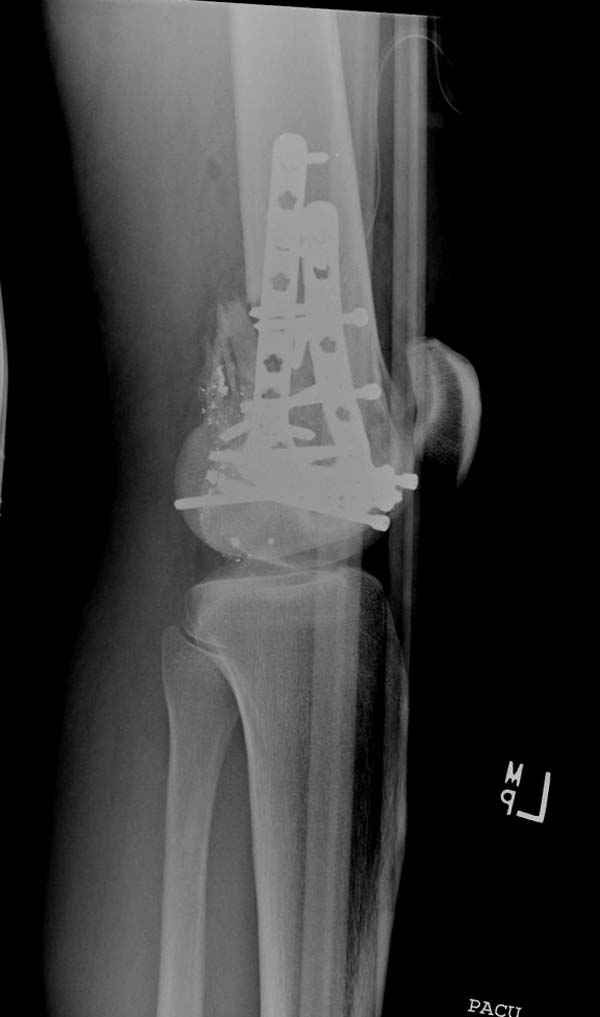

По Густило и Андерсену все high-energy переломы являются III не зависимо от степени повреждения мягких тканей. Plating такого перелома на второй день кажется немного рискованным хотя "победителей не судят". Судя по КТ, медиальный мыщелок стабильный, насколько необходимо было его фиксировать?

Красиво и быстро?! - две пластины + 18 шурупов.

Идеальная репозиция?! -На снимочке A-P проeкции видна "зазубрина" по суставной поверхности, латеральный снимок - тоже не идеально.